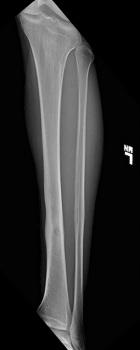

25 year old male with six months left shin pain that wakes him up at night, worse with activity, better with Aleve

Zoom image: Radiological image Radiological image.